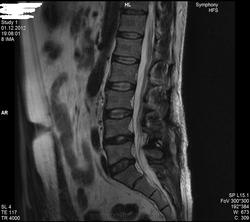

Уважаемые специалисты. МРТ после операции 8 нед.

Операция геминоламинэктомия L4-5 с установкой системы динамической стабилизации между остистыми 4-5.

После операции боли в пояснице прошли, боль в коленях и голенях осталась в неизменном виде. Ниже верхней трети голени боль не опускается.

По задней стороне туловища в ногах болей никогда не было. Уважаемый специалист, к сожалению не рентгенолог, утверждает что нет никаких признаков радикулопатии. Не посмотрите своим профессиональным взглядом.